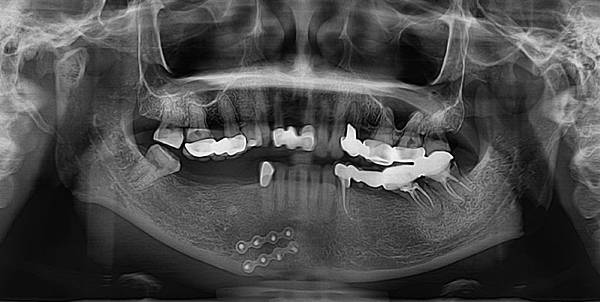

↑第一次照X光,很明顯的看得出我右側下顎缺牙,右側上顎牙橋內大臼齒斷裂。

就在我原本只是想用假牙來裝飾門牙缺牙的慘狀,沒想到臼齒、犬齒相繼掉牙,忍了好長一段時間,終於又再度踏入牙醫診所,好好諮詢該怎麼解決我缺牙嚴重的問題了!透過網路鄉民的介紹和推薦,也好好爬文查了郭德樑牙醫診所的口碑之後,發現台中對於人工植牙手術的技術推薦,多數人都推薦郭醫師的技術,因此抱著希望預約看診。第一次就診時,郭醫師先幫我清潔口腔後,也拍了X光片告訴我目前牙齒狀況,也順便幫我清潔假牙附近的口腔衛生,經過X光片,也發現我原本裝假牙套的牙齒出現斷裂,這是我想都沒想過的問題,原本只覺得那幾牙痛,應該是小蛀牙引起,沒想到卻是牙齒已經斷裂,還包覆在假牙套裡~